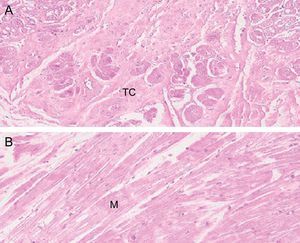

Estudio histológicoDe los 41 corazones estudiados, en 5 de ellos se obtuvieron muestras para histología de los FT. Para ello se conservaron mediante formol, y posteriormente se cortaron y tiñeron mediante hematoxilina-eosina y tricrómico de Masson. Realizamos microfotografías a 10, 20 y 40 aumentos (figura 2).

Resultados del estudio histológicoLa histología de los FT fijados y estudiados muestra fibras musculares y de tejido conectivo en distintas proporciones según la localización del corte. La vascularización de los FT fue evidente en los cortes (figura 5).

Los resultados mediante disección cadavérica de corazones humanos demuestran que la presencia de FT es la norma sin excepción, con una media de entre 3 y 4 FT encontrados. Esta frecuencia es la mayor de las halladas en estudios previos4, ya que en series cortas de animales se había hallado hasta en un 95%16. La histología, como en estudios anteriores, muestra que están compuestos por fibras de colágeno y musculares en distinta proporción, pero son más frecuentes las fibras musculares en los FT de mayor grosor. Esto ha permitido clasificarlos en 2 grupos: musculares y tendinosos, aunque no se sabe si funcionalmente son distintos. Las tinciones realizadas no permitieron visualizar las estructuras de trasmisión eléctrica, si bien hay estudios que refieren su presencia y su implicación en las arritmias cardiacas19,20,26.